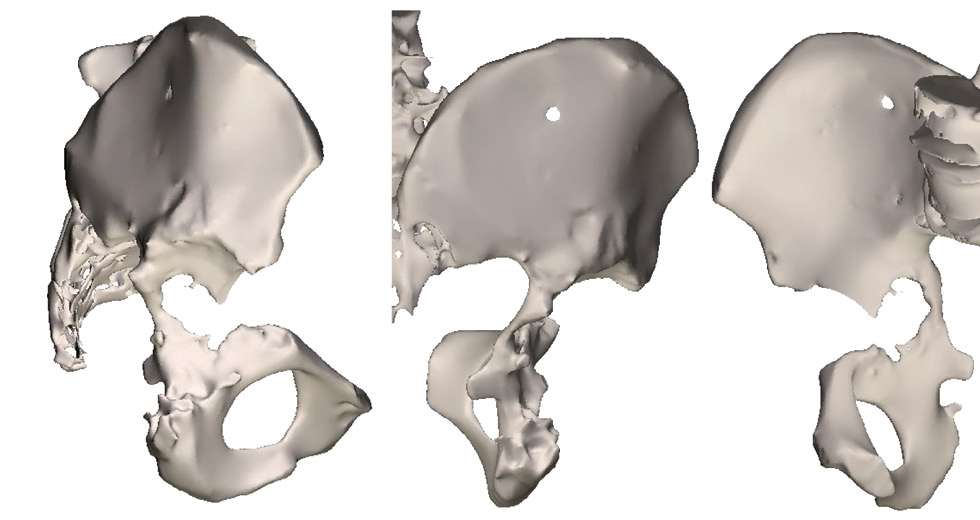

Three months after surgery, the patient came for a follow-up examination. Radiographs showed migration of the sciatic and brow bones from the flanges of the construct (Fig. 7). The patient still had pain syndrome in the operated joint area, which was 28 (mm) points on the VAS scale. On the HHS scale, the hip joint function was assessed at 75 points. The social adaptation score on the WOMAC scale was 38 points. Considering the clinical and radiological picture, the patient was offered surgery for screw removal from the lower flanges and correction of the sciatic flange of individual design with a high-speed bur. The patient refused the proposed surgery.

Fig. 7. Postoperative control X-ray after 3 months.

Six months after surgery, no negative dynamics on control radiographs were observed. The HHS, WOMAC, and VAS scores were 82, 15, and 30 (mm) points, respectively. Despite a slight increase in the severity of pain syndrome according to the VAS score, the patient noted improvement in the bearing capacity and functional results of the operated limb. No significant changes in the evaluation scales were noted at the subsequent follow-up examinations (1 year after surgery and once a year thereafter). At the time of writing, >4 years have elapsed since the operation. Data obtained four years after surgery did not show negative dynamics on control radiographs (Fig. 8). The pain syndrome slightly increased and corresponds to 32 (mm) points on the VAS scale. On the HHS scale, the hip joint function corresponded to 74 points, and social adaptation according to the WOMAC scale corresponded to 35 points. The patient is under dynamic observation.

Fig. 8. Postoperative control X-ray 4 years after the operation.